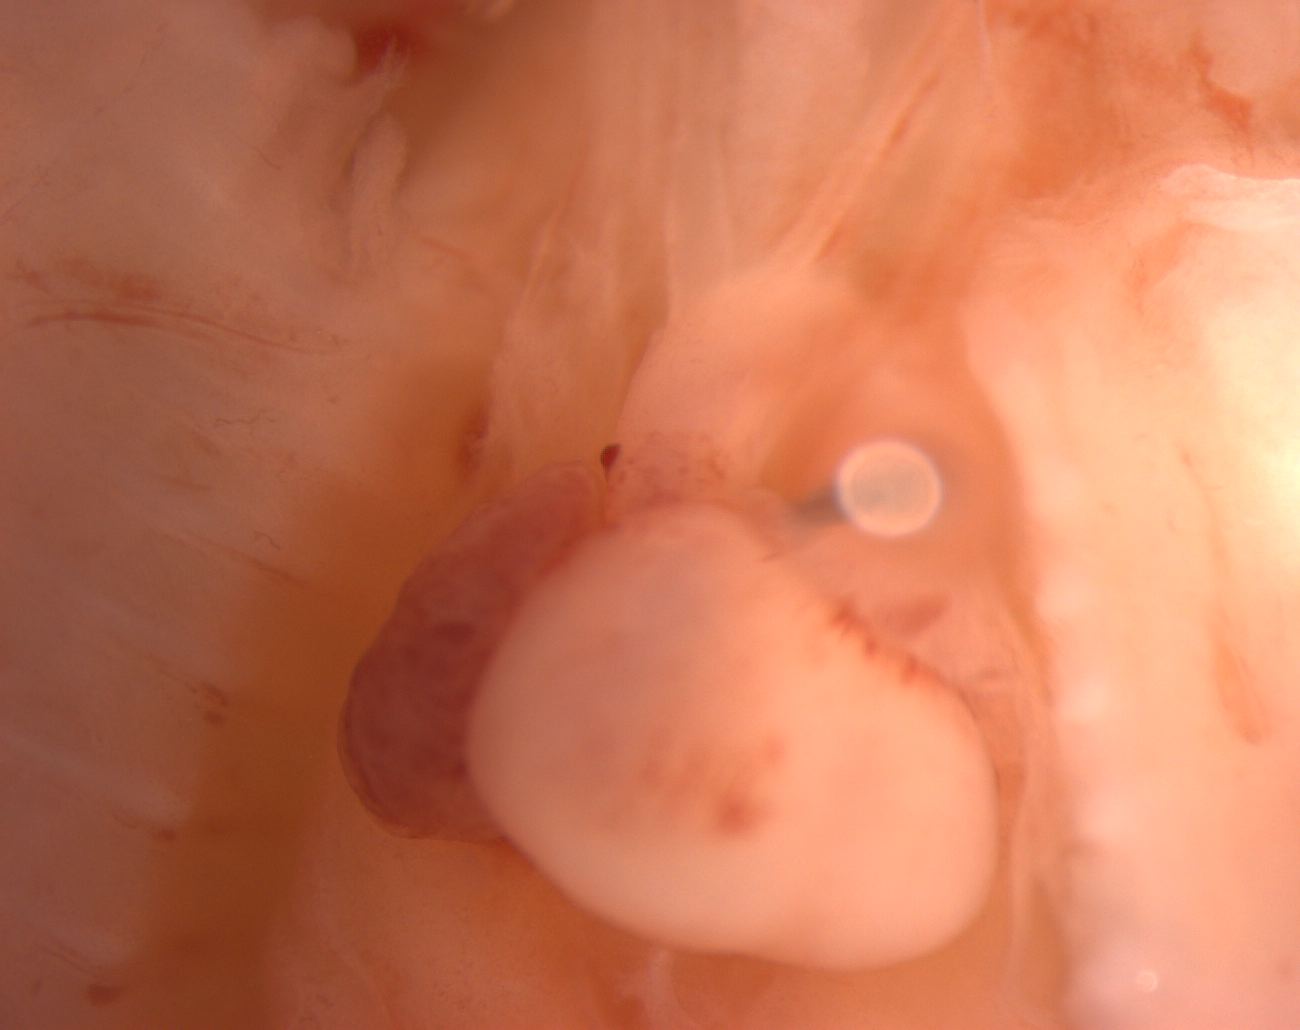

Caption Mutant 012-003-2 (E16.5) presents with PTA

Copyright This image is from the Laboratory of Dr. Cecilia Lo, a member of the Cardiovascular Development Consortium (CvDC), Bench to Bassinet (B2B) program of the National Heart Lung and Blood Institute (NHLBI), and is displayed with the permission of the authors. J:175213

Cplane1b2b012Clo ciliogenesis and planar polarity effector 1; Bench to Bassinet Program (B2B/CVDC), mutation 012 Cecilia Lo

Cplane1b2b012Clo/Cplane1b2b012Clo C57BL/6J-Cplane1b2b012Clo